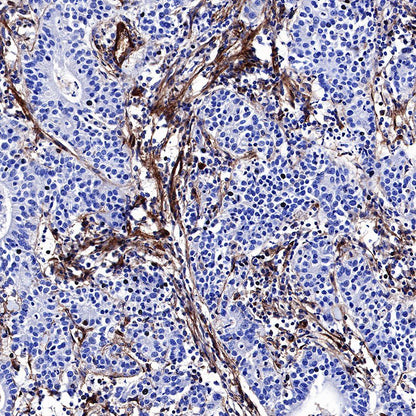

IHC shows positive staining in paraffin-embedded human lung squamous carcinoma. Anti-CD39 antibody was used at 1/500 dilution, followed by a HRP Polymer for Mouse & Rabbit IgG (ready to use). Counterstained with hematoxylin. Heat mediated antigen retrieval with Tris/EDTA buffer pH9.0 was performed before commencing with IHC staining protocol.